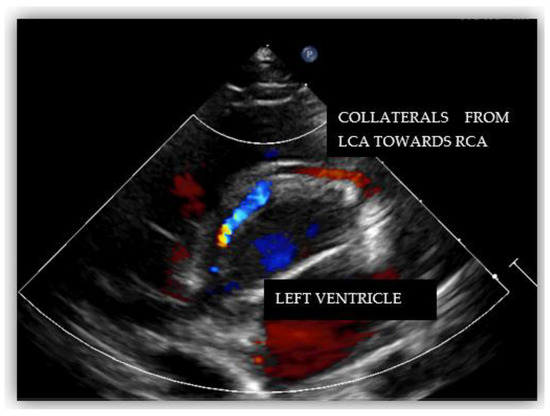

Anomalous origin of the right coronary artery from the pulmonary artery (ARCAPA) is a rare congenital coronary anomaly, with an uncertain prevalence and often diagnosed incidentally. This case report presents a 62-year-old male with ARCAPA diagnosed during an evaluation for chest surgery. The patient had a history of colon cancer and active tuberculosis, complicating the clinical management. He reported chest pain, shortness of breath, and palpitations, with atrial fibrillation observed on a 24 h Holter ECG. Coronary angiography revealed robust collateral circulation and a suspected anomalous origin of the right coronary artery, confirmed by CT imaging. The patient’s stress MRI showed mildly reduced left and right ventricular ejection fractions and perfusion deficits in the apical segments (2/17) of the septal and inferior walls. Given the patient’s comorbidities, including active tuberculosis, the Heart team decided on a non-operative management approach, focusing on careful monitoring and pharmacological management rather than immediate surgery. This case emphasizes the complexity of managing ARCAPA in the context of significant comorbidities, highlighting the importance of individualized, multidisciplinary treatment strategies. Early diagnosis using advanced imaging techniques is crucial, and a non-operative approach can be considered in patients with preserved left ventricular function and no significant ischemia, as demonstrated in this case. Full article

Show Figures

Figure 1